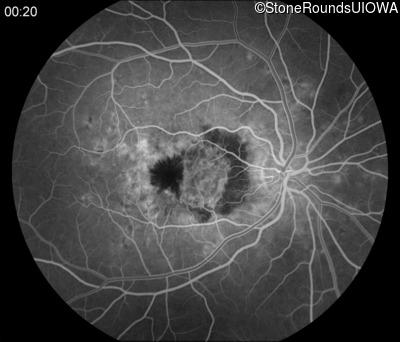

Fluorescein Angiography - Right - 20/250

Exemplar